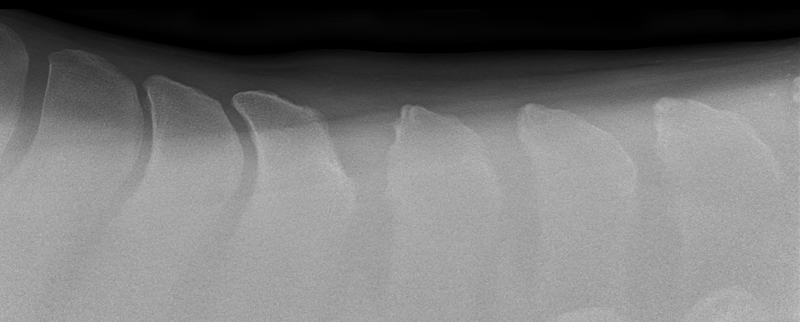

SEVERE CASE OF KISSING SPINES SEEN BY X-RAY

Overriding dorsal spinous processes

X-RAY COURTESY OF VIRGINIA EQUINE IMAGING

Kissing Spines, more scientifically known as impingement of the dorsal spinous processes, is a condition that has grown in relevance and impact throughout the last two decades with improved diagnostics and education. It’s hard not to feel a horse’s pain after taking just one look at an x-ray that indicates Kissing Spines. The condition can diminish athletic performance and render a horse unusable in severe cases, while other cases with the ugliest x-rays can experience no pain or performance implications. While still shrouded in some level of mystery, Kissing Spines is known to be conformational and most likely genetic. When spinous processes are conformationally close together they will inevitably contact, with that continual contact causing the modeling changes that are classically seen on radiographs.

Though Kissing Spines can be seen clearly in diagnostic imaging, truly understanding the nuances of the condition and how it can vary patient-to-patient is where things become less well-defined. Dr. Cliff Honnas, equine veterinarian, surgeon and founder of the widely respected Texas Equine Hospital in Bryan, Texas, is a sought-after authority figure in all things related to this condition, especially concerning its surgical treatment. “Kissing Spines is a condition where the dorsal spinous processes are too close together,” he explains simply. “These are the bones that make up the backbone of the horse directly underneath the saddle.” Normal horses should typically have a five millimeter or larger space between those bones, depending on the breed and size of the animal in question. In Kissing Spines cases, however, that space can be minimally to drastically narrowed until those bones are close together, touching or overriding.